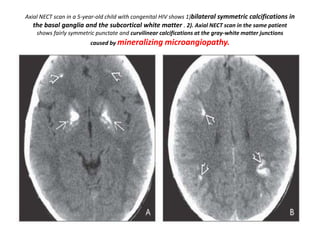

Axial NECT scan in a 5-year-old child with congenital HIV shows 1)bilateral symmetric calcifications in

the basal ganglia and the subcortical white matter . 2). Axial NECT scan in the same patient

shows fairly symmetric punctate and curvilinear calcifications at the gray-white matter junctions

caused by mineralizing microangiopathy.